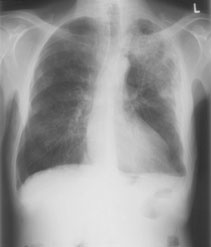

Ihnen wird ein 62-jähriger Patient vorstellig, der seit zwei Wochen subfebrile Temperaturen hat, Husten und leichter Auswurf bestehen ebenfalls. Status nach Zystekomie und Ileum-Pouch sowie Prostatovesikulektomie vor knapp zweieinhalb Jahren bei Plattenepithelkarzinom der Harnblase (pT2 G3).

Klinisch zeigt der Patient einen stabilen Allgemeinzustand. Die Lungenauskultation ist unauffällig. Im Labor ist das CRP auf über 160 mg/l erhöht. Das Thoraxröntgen ergibt folgendes pa Bild: